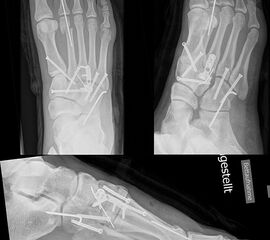

Patienten mit einer isolierten Verletzungen des Lisfranc Ligaments Grad II und III (n. Nunley) profitieren von einer operativen Therapie (Abb. 13).

Zum Lesen der Bildbeschreibung und zur Vollansicht bitte das Bild anklicken.

Bei frischen Verletzungen gelingt meist die geschlossene Reposition durch eine Repositionszange unter Bildverstärkerkontrolle. Anschließend wird über eine kleine mediale Inzision ein Kirschnerdraht vom Os cuneiforme mediale in die Metatarsale II-Basis gebohrt und das Lisfranc-Ligament durch eine Stellschraube in anatomischer Stellung ruhiggestellt. Durch weitere Schrauben lässt sich bei Bedarf das Tarsometatarsale I-Gelenk und der Raum zwischen Os cuneiforme I und II stabilisieren. Nach Lagekontrolle unter dem Bildverstärker wird eine durchbohrte Schraube mit durchgehendem Gewinde eingebracht (Abb. 14). Von der Verwendung von Zugschrauben wird abgeraten, da diese eine unnötige und unphysiologische Kompression der Gelenkflächen erzeugen.

Verwendet werden kanülierte oder Standard-Kleinfragmentschrauben. Die Verwendung von 2,0 mm Kirschnerdrähten ist ebenfalls möglich. Hier besteht allerdings ein erhebliches Risiko der Lockerung und Dislokation 15. Thordarson und Hurvitz (2002) 16 berichten über den Einsatz von resorbierbaren Schrauben. Gelingt die geschlossene Reposition nicht, was insbesondere bei verzögerter Diagnostik der Verletzung aufgrund der ausgeprägten Narbenbildung zwischen dem I. und II. Strahl der Fall sein kann, so wird über einen dorsalen Zugang das Narbengewebe ausgeräumt und anschließend nach Reposition die durchbohrte Schraube gesetzt. Postoperativ schließt sich eine achtwöchige Phase mit vollständiger Entlastung an. Der Patient ist darauf hinzuweisen, dass eine höhere Belastung des Fußes ein hohes Risiko des Schraubenbruches beinhaltet und dass eine gebrochene Schraube schwierig zu entfernen ist. Eine Teilbelastung mit 20 kg wird in Verbindung mit einer nach Fußabdruck angefertigten Einlage nach der achten Woche erlaubt. Die Metallentfernung erfolgt 12 Wochen postoperativ. Anschließend wird die Belastung auf das volle Körpergewicht gesteigert. Der Trainingsaufbau erfolgt stufenweise. Radfahren und Schwimmen ist rasch nach der Metallentfernung möglich; mit einem Lauftraining kann 4 Wochen nach der Metallentfernung begonnen werden. Bis zur Rückkehr in den Wettkampfsport vergehen erfahrungsgemäß 6 Monate. Das Tragen einer abstützenden Einlage wird für mindestens 1 Jahr empfohlen, wobei nach 6 Monaten von der statischen Abstützung zu sensomotorischen Einlagenkonzepten gewechselt werden kann (Abb. 15).

In der Regel werden die physiologisch rigiden TMT-1 bis 3 mittels Schrauben transfixiert. Hierfür werden meist kanülierte Kleinfragment-Kortikalisschrauben (3,5 oder 4 mm) verwendet. Diese können in Stellschraubentechnik von der Metatarsale-1-Basis in das Os cuneiforme mediale (Abb. 17) sowie vom Os cuneifome mediale in die Metatarsale-2-Basis und bei zusätzlicher intercuneiformer Instabilität vom Os cuneifome mediale in das Os cuneifome intermedium eingebracht werden.

Ggf. wird zusätzlich ein K-Draht oder eine Schraube von der Metatarsale-2-Basis in das Os cuneiforme intermedium gebohrt (Abb. 18). Zur Transfixation der TMT-4 und 5-Gelenke werden, entsprechend ihres höheren physiologischen Bewegungsumfangs meist K-Drähte empfohlen. Die Indikation zur Transfixation wird von den meisten Autoren nur bei einer Instabilität gesehen, einige empfehlen eine Transfixation sämtlicher TMT-Gelenke unabhängig vom Ausmaß der Instabilität 10. Kleine, nicht refixierbare Fragmente sollten entfernt werden. Ist ein primärer Hautverschluss nicht möglich, erfolgt die temporäre Weichteildeckung mit Kunsthaut wie Epigard 112951710.